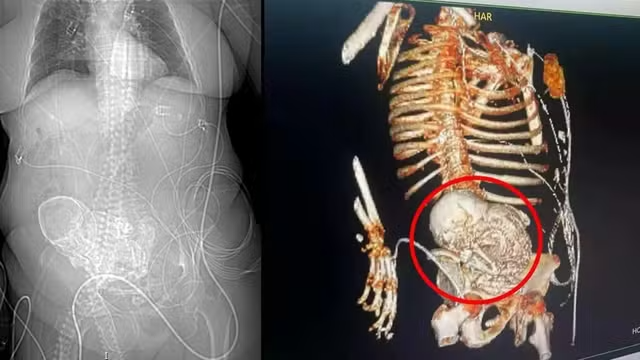

Daniela deu entrada no Hospital com um quadro de infecção grave em 14 de março. Conforme nota, divulgada nesta terça-feira (19) pelo Hospital Regional Dr. José de Simone Netto, no mesmo dia uma tomografia em 3D diagnosticou a presença de feto calcificado – condição rara chamada de litopedia, consequência de uma gravidez ectópica (gestação em que o óvulo fertilizado é implantado fora do útero) que evolui para morte fetal e calcificação.